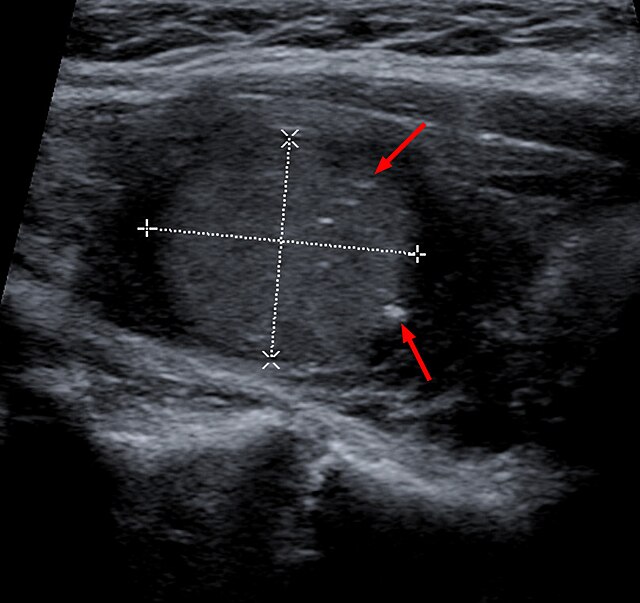

Фотографии опухоли медуллярной аденокарциномы